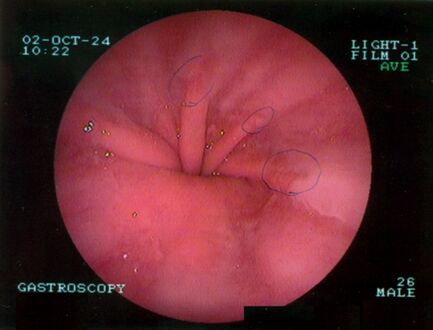

تنظير الجهاز الهضمي العلوي يصور الفتق الحجابي.

-

تنظير الجهاز الهضمي العلوي في وضع الانثناء للخلف يظهر الفتق الحجابي من النوع الأول.